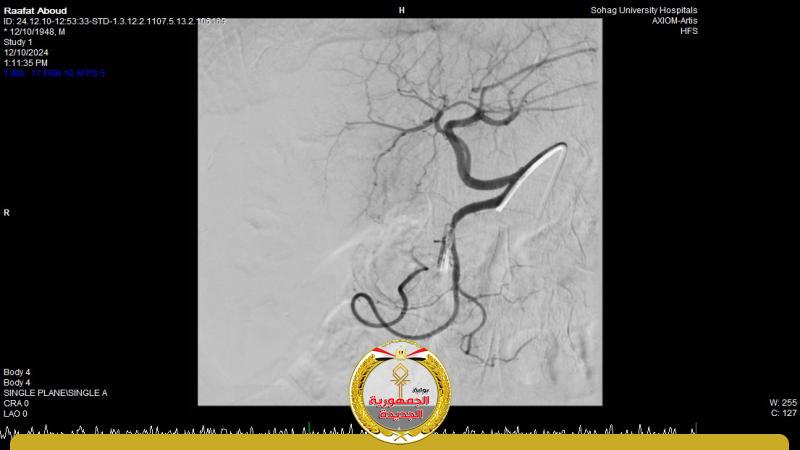

وأضاف الدكتور أحمد كمال المدير التنفيذي للمستشفيات الجامعية انه بعد اجراء الفحوصات للمريض تبين وجود قرحة كبيرة بالاثني عشر وشريان نازف، حيث نجح الفريق في التحكم المبدئي بالنزيف عن طريق تركيب مشبك معدني بالمنظار وحقن للقرحة النازفة، ثم تم استدعاء فريق أطباء وحدة الاشعة التداخلية علي الفور وتم عمل غلق للشريان النازف بشكل عاجل من خلال جهاز القسطرة.

وأوضح الدكتور محمد زاكي رئيس قسم الأشعة أن مثل هذه الحالات تعد من الطوارئ الطبية الخطيرة والتي تستوجب عمل قسطره شريانية عاجلة لغلق الشرايين النازفه مشيراً أن وحدة الأشعة التداخلية تم تزويدها بجهاز أشعه محوري متقدم لاجراء مثل هذه الحالات، وأن هذا النجاح هو نتيجة لتعاون أقسام المستشفي مع وحدة الأشعة التداخليه لتقديم خدمة مميزه للمرضي.